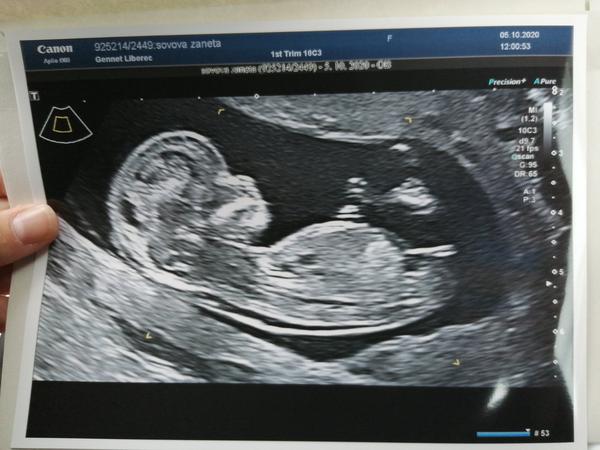

@twins_sovovi mě v Gennetu řekli v 16.tt.

@twins_sovovi V mém prvním těhu ve 12. týdnu nebylo na ultrazvuku pohlaví vidět. Holčičku nám řekli až v 16. týdnu, kdy jsem si ze zvědavosti zaplatila navíc vyšetření pohlaví. A teď jsem pár dnů po ultrazvuku v druhém těhotenství a tam ve 14. týdnu viděli hned jasného chlapečka 😍

@petuliiik01 jezinky to je super že máš parecek😍 Jsem napnuta jak guma u spoďárů dneska jdeme tak jsem zvědavá 😍😍 mě tenkrát před 10 lety řekly pohlaví až na 20 tt 😃 tak doufám že to nebude nejakej stydlin a nebude nas napinat🤗🤭🤭🤭

@mikejla_a ahojky zapomela jsem napsat 🤭 šlo vidět krásně a čekáme 3ti holčičku 😃😍💞